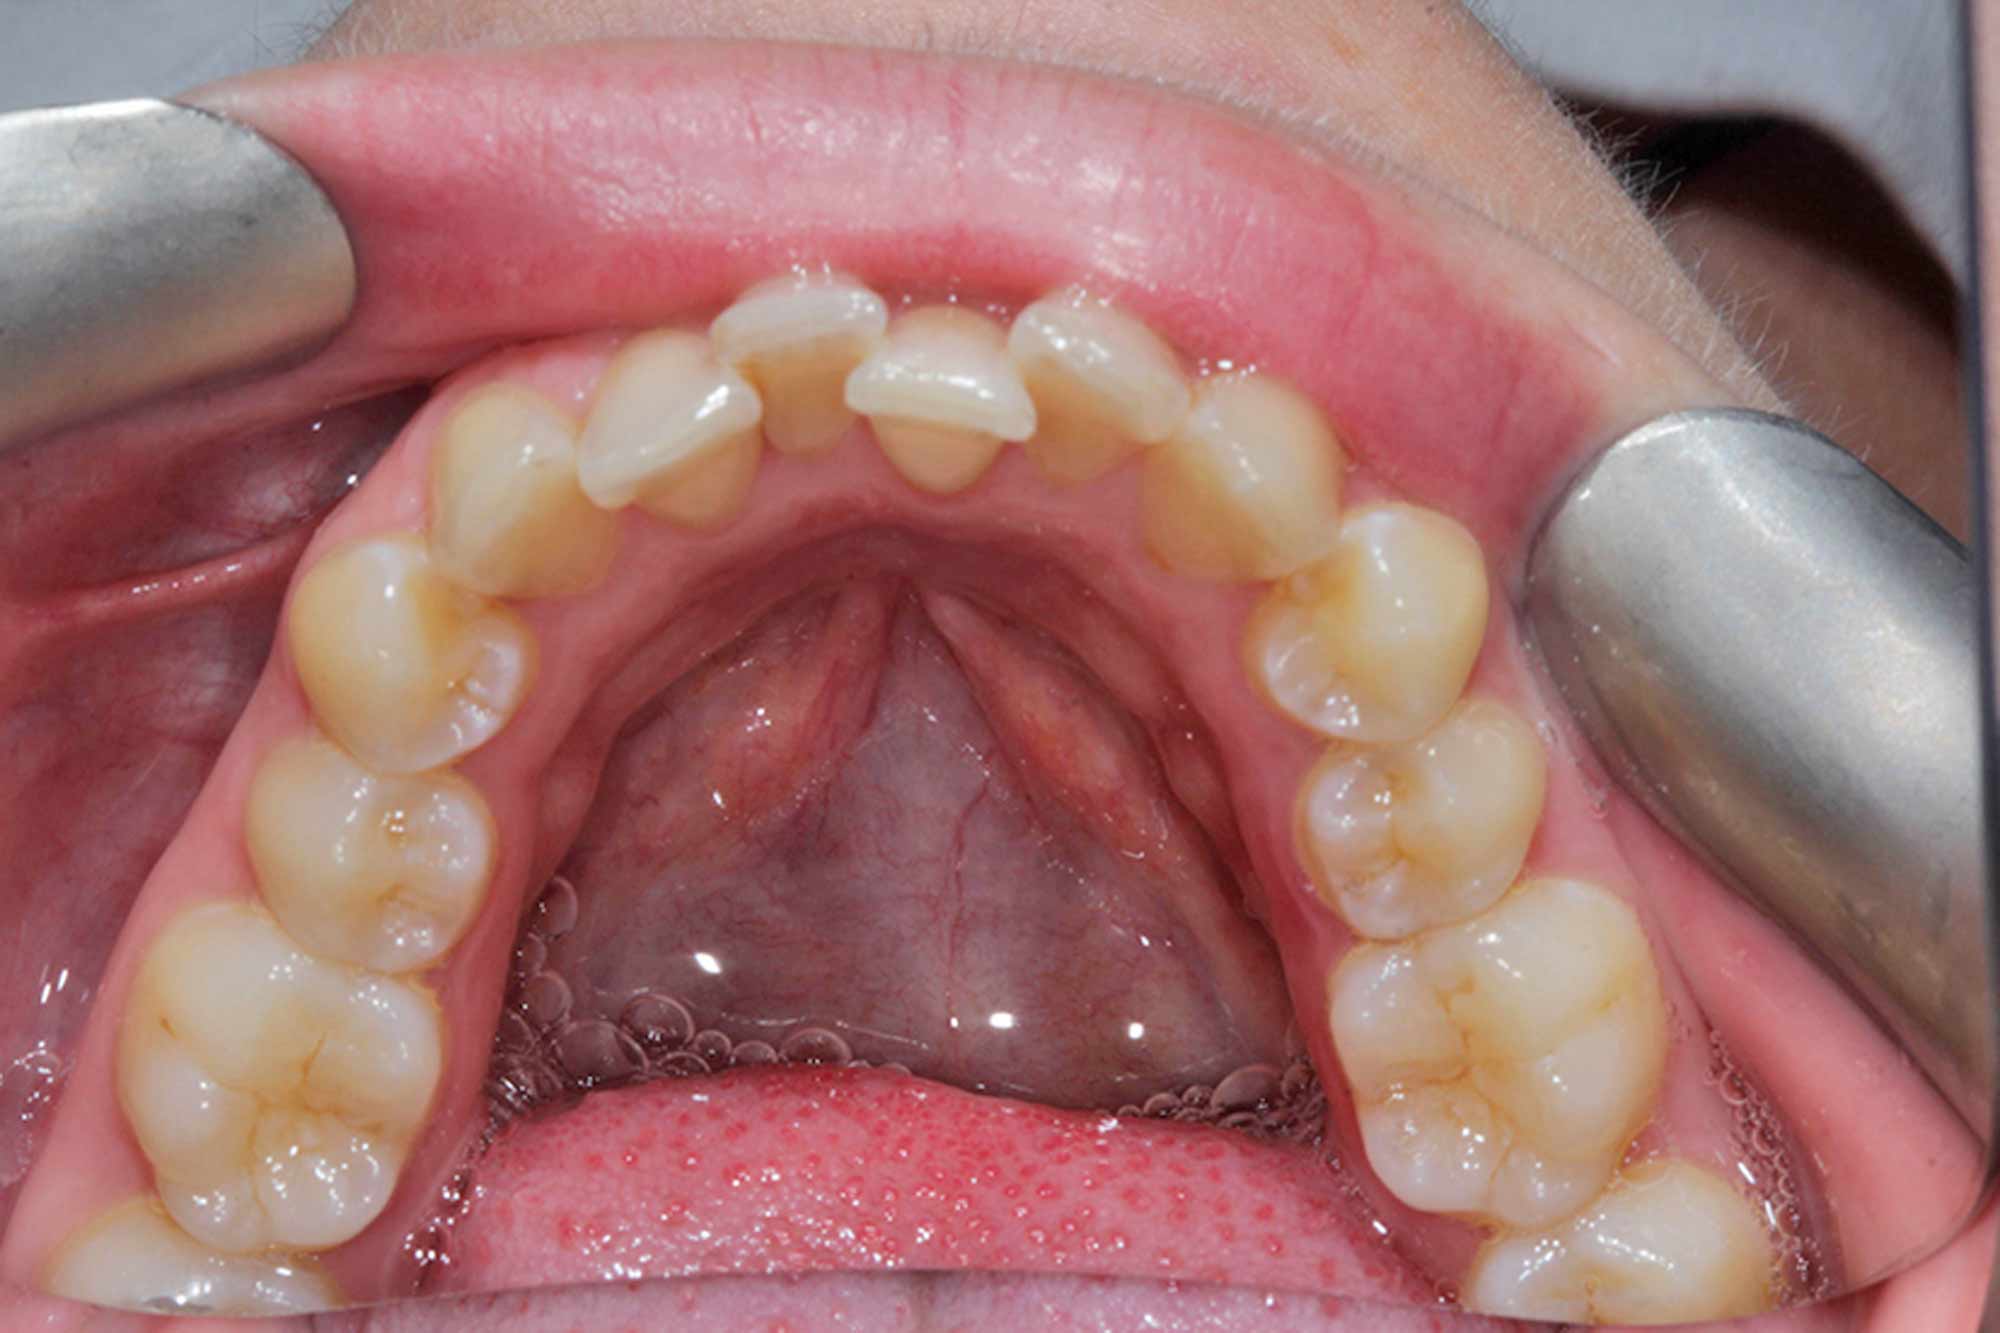

The Invisalign Clincheck software gave us a lovely representation of the end result. It also allowed us to share, realistically, what other treatments would be needed at the end of the alignment phase so the patient was fully aware.

In my opinion, it is one of the best pieces of smile design software currently on the market for orthodontics, without a shadow of a doubt!

In this case, 14 aligners were needed to achieve the outcome we were looking for. This was followed by two short stages of refinements, as we certainly aimed for perfection in the end result and strived to match the original Clincheck prediction.

She was the ideal patient for this treatment, as we were both on the same page throughout. She was fully aware the final outcome would be more than nine months away before we embarked on her treatment.